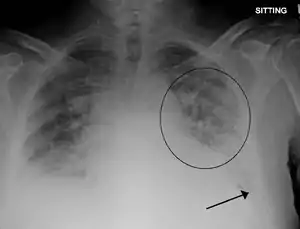

| ادم و خیز ریوی همراه افیوژن در هر دو سمت جنب. | |